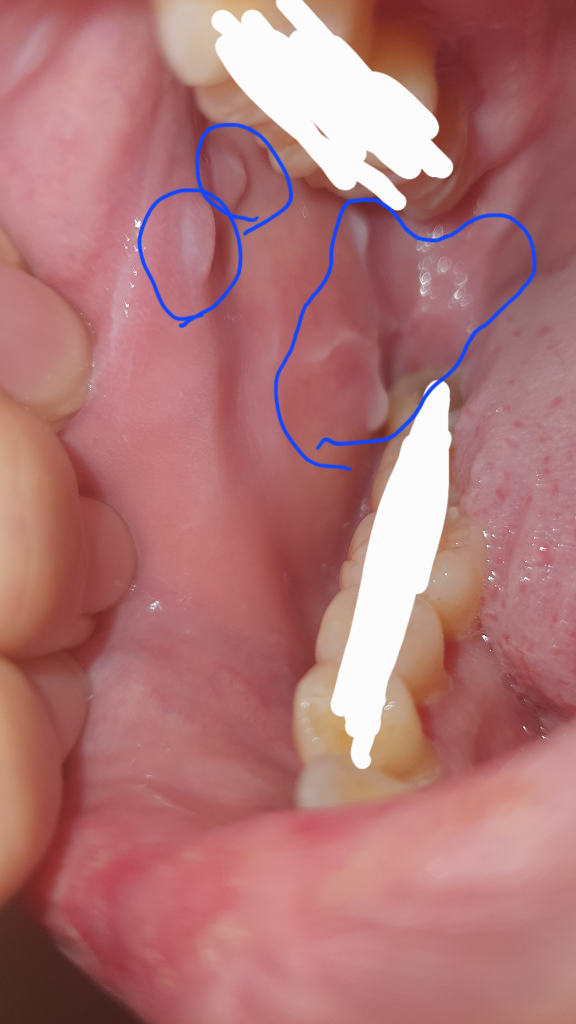

우연히 입 안을 봤는데 양쪽 다 무언가가 볼록 튀어나오고(물컹거림), 흰 줄이 마치 이빨 자국처럼 이빨이 닿는 부위에 나있는데 이게 뭔가요? 전혀 아프지는 않고 언제 생겼는지도 모르겠어요. 병원을 가야한다면 무슨병원을 가야할까요?

• 1번 째 사진